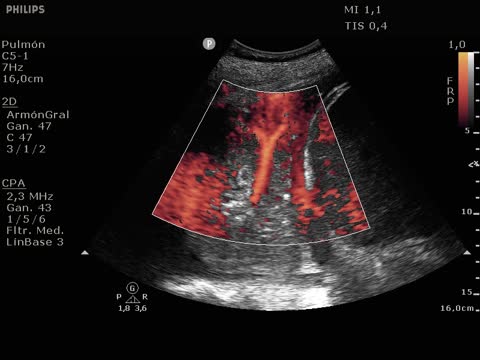

On day 22 of admission, he experienced sudden respiratory and hemodynamic worsening, with a need for vasoactive drugs and increased FiO2 demands. There was no fever or elevation of infection markers. Echocardiography discarded indirect signs of pulmonary thromboembolism. The chest radiography (Fig. 1 Image A) evidenced a clear worsening of the right hemithorax. Pulmonary ultrasound in turn revealed a pattern C (Fig. 1 Image B) in the right lung base that could correspond to atelectasis or pneumonia. Color Doppler (Appendix A image C and enclosed video) revealed a tree-like color sign, corresponding to blood hyper-flow. This finding, together with the dynamic pattern C (fluctuating with inspiration) was consistent with pneumonic condensation.